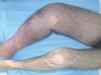

Mujer de 83 años, con antecedente de cáncer de mama y tratada mediante mastectomía y radioterapia. Como consecuencia del tratamiento desarrolló un linfedema en el miembro superior derecho, ipsilateral a la mama mastectomizada. A los 10 años de este tratamiento, apareció sobre el linfedema una placa eritematoviolácea de 5 cm de diámetro, bien definida e indurada (fig. 1). El examen histológico reveló que la lesión correspondía a un angiosarcoma (confirmado por técnicas de hematoxilina-eosina y técnicas de inmuohistoquímica (CD34 positivo). Se instauró un tratamiento con radioterapia, con buena respuesta. La paciente presenta una lesión residual y continúa en seguimiento por nuestra parte y el servicio de oncología.

Fig. 1.--Angiosarcoma localizado, en paciente sometida a mastectomía y radioterapia.